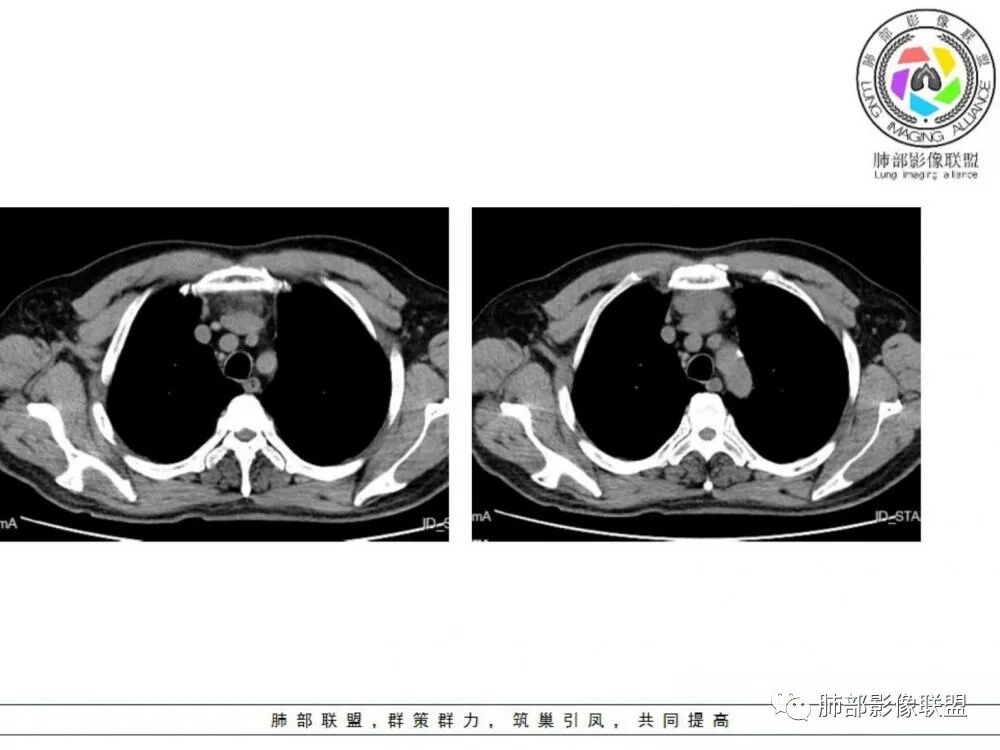

男性患者,65岁,前胸后背疼痛一个月。影像学前上纵隔分叶状的软组织肿块,肿块形态怪异,偏软,位于大血管间隙前,并有向血管后间隙发展的趋势,平扫CT值为40左右,增强扫描中心部未见强化,周围轻度的强化,约为50左右。前上纵隔的疾病谱包抬胸廓内甲状腺肿、胸腺瘤/癌、畸胎瘤、淋巴瘤。少见的心包囊肿或支气管囊肿。根据肿块的形态及强化特点,首先还是排除了胸内甲状腺肿及胸腺来源的肿物,这类的肿物强化比较明显。畸胎瘤成分比较复杂,具有软组织钙化或者脂肪类的组织,这个肿物虽然在平扫的时候好像有斑点状的钙化灶,但是总体成分还是比较单一,所以还是排除畸胎瘤的诊断。所以这样的情况是考虑:淋巴类的肿瘤,注意排除心包的囊肿或支气管来源的囊肿。

老年男性患者,前膈软组织肿块,边缘轮廓不光整,边界似乎尚清晰,内见小点状钙化灶,平扫密度欠均匀,增强后轻度强化表现,边缘有些斑片状的高强化区。综合考虑胸腺瘤或胸腺鳞癌,神经内分泌癌强化弱了一些。患者年龄较大,生殖细胞肿瘤不考虑,淋巴瘤血管包绕不够,可能性不大

老年男性,前纵隔不规则软组织肿块影,密度欠均匀,与大血管分界欠清,上腔静脉局部包绕受侵,增强扫描不均匀轻度强化,PET-CT高代谢。考虑恶性肿瘤性病变,胸腺癌可能。鉴别淋巴瘤。

前纵隔胸腺区分叶状软组织肿块影,轻度不均匀强化,中心可见坏死,边缘不清,病灶与邻近心包见条索影,上腔静脉受侵,上纵隔多发小淋巴结,考虑胸腺鳞癌可能。

男性患者,65岁,前胸后背疼痛一个月。胸部影像:前上纵隔分叶状的软组织肿块,形态不规则,包绕大血管生长趋势,与周围分界不清,密度较均匀,呈多结节融合,肿块周围可见肿大淋巴结,内乳动脉旁淋巴结大,上腔受累,肿物内可见低密度区,增强扫描周围轻度强化。考虑:恶性病变,淋巴瘤?胸腺神经内分泌肿瘤?鉴别胸腺瘤

老年男性,前纵隔肿块,形态不规则,右侧内乳动脉增粗,与血管脂肪间隙模糊消失,定性恶性,周围多发小淋巴结,有斑点状钙化灶,增强中心低密度区无强化,边缘强化为主,首先考虑胸腺鳞癌,鉴别胸腺瘤。

中老年男性,前纵隔占位,基本居中,向两侧生长;边缘膨隆分叶,部分边界不清,增强不均匀轻中度强化,坏死区边界不清;周围多发增大淋巴结,考虑恶性。主要在胸腺癌、胸腺瘤、淋巴瘤之间鉴别。病灶偏软,有钻缝样生长,这些征象偏向于淋巴瘤。但此例老年患者,病灶内有点状钙化,缺乏结节堆砌感,倾向胸腺癌诊断。